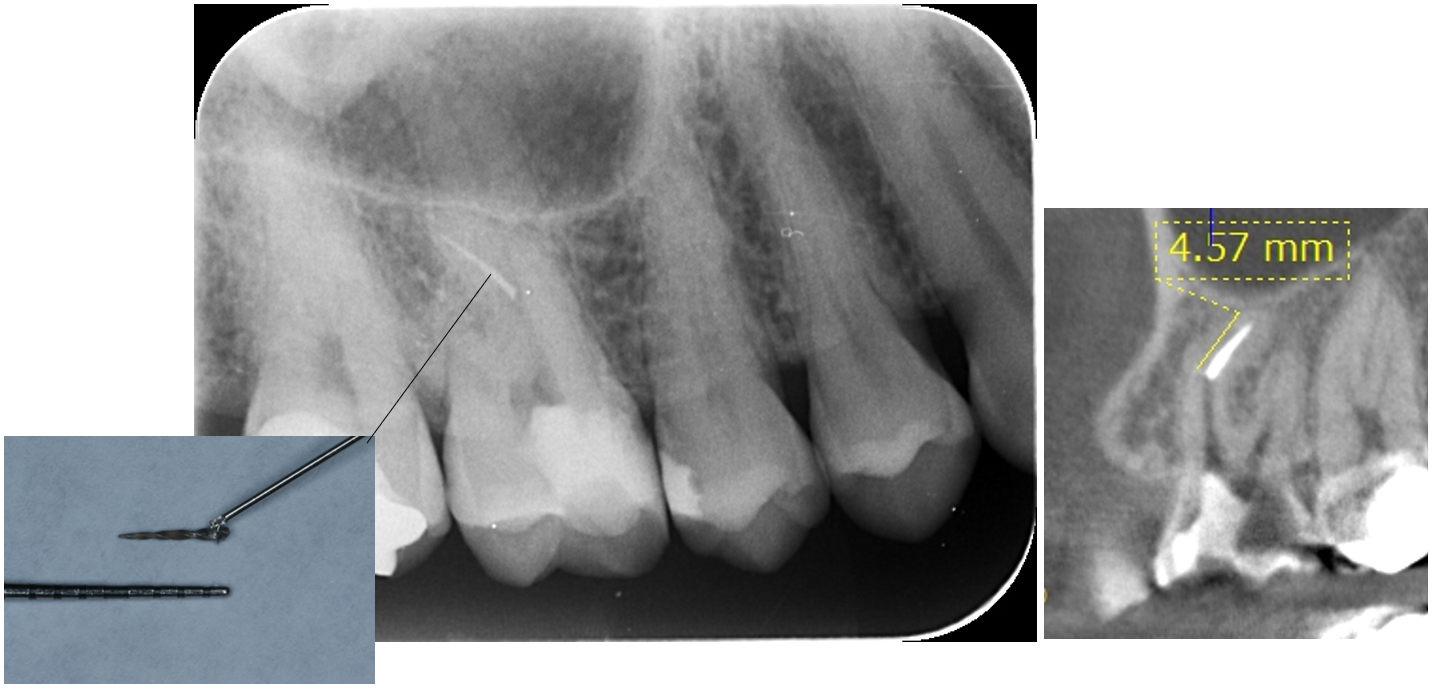

症例4

| 来院時の主訴 | 「他院で治療後、器具が歯の中で折れてしまったと言われた。治療の続きからお願いしたい。」 |

| 医院の診断 | 歯根の湾曲、人為的破折ファイルの存在 |

| 通院期間 | 1ヶ月 |

| 来院回数 | 3回 |

| 治療費 | 総額:200,000円(税抜) 【内訳】 精密感染根管治療100,000円、ファイバーポストコア20,000円、ダイレクトボンディング治療80,000円 |

| リスクと副作用 | ①根管治療歯は長期的には破折するリスク ②メインテナンスが必要 |

| ここがこだわりのポイント!☝ |

4.5mm以上の破折ファイルは除去しにくいと言われています。 今回は折れてしまった破折ファイルを事前にレントゲンでチェックした所4.57mmありました。破折ファイルはループと言われる特殊な器具を用いて短時間で除去することができました。 |